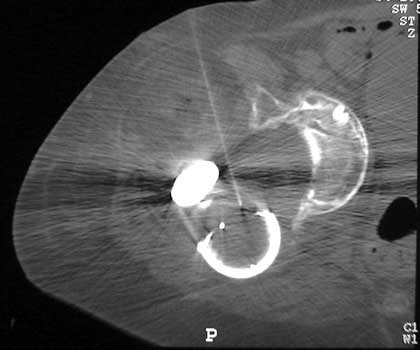

Dislocated femoral component and acetabular cup in grossly loose arthroplasty. CT guided aspiration to rule out infection.